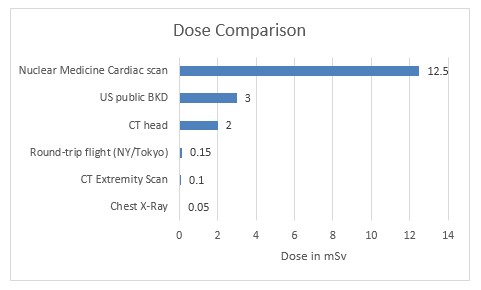

تُعد جرعة الإشعاع الجزء الآخر من المعادلة. فبواسطة عمليات التصوير المقطعي المحوسب، يمكن للفنيون حماية أنفسهم أو الحدّ من التعرّض لجرعات الإشعاع من خلال الخروج من الغرفة أو الوقوف خلف حاجز أثناء الإجراء. إلا أن المرضى الذين يخضعون إلى العلاج فهم يتعرضون إلى الإشعاعات. ولكن، على الرغم من أن التصوير المقطعي المحوسب يزيد من الأعباء التي تتسبّب بها الجرعة الإشعاعية، دعونا نناقش هذه التقنية بكل موضوعية. إن كمية إشعاع "الخلفية" الذي نتعرض له جميعًا سنويًا هو بالفعل أعلى في المتوسط من بعض عمليات مسح التصوير المقطعي المحوسب. ألق نظرة على هذا الرسم البياني: